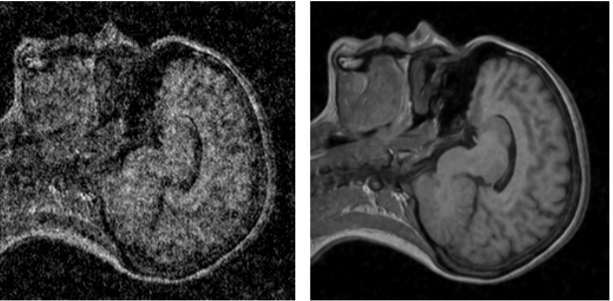

Помимо применения техники в фотографии, в частности в астрофотографии или съемке в темноте, разработчики также предложили применять ее для повышения качества снимков МРТ и продемонстрировали примеры работы алгоритма на таких снимках:

Фото: arxiv.org